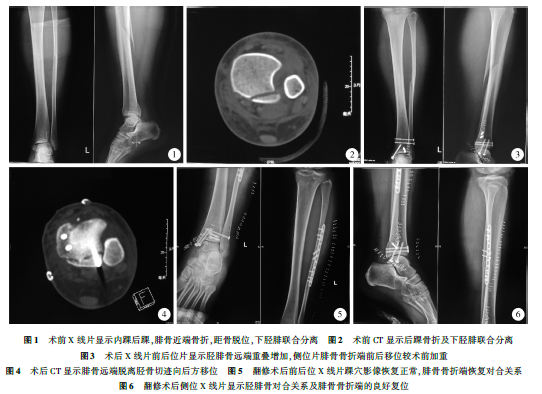

患者,女,20岁,骑车倒地致踝部扭伤后12h入院,体格检查显示踝部及小腿肿胀明显,压痛,皮肤完整,末端血液循环正常,像学检查显示腓骨近端骨折移位、下胫腓联合分离、内踝骨折移位、后踝骨折、距骨脱位(图1),CT图像显示下胫腓联合分离,骨远端向后移位(图2)。

经完善术前准备,于伤后24h安排手术治疗。手术在全身麻醉下进行,于踝关节外侧沿腓骨远端微创切口,显露腓骨外侧骨皮质后使用复位钳内外方向挤压胫腓骨,术中影像显示踝穴宽度恢复,维持复位,经腓骨远端切口安装2枚螺钉维持复位,内踝处弧形切口显露内踝,复位后使用2枚空心拉力螺钉固定,踝关节前方切口,显露胫骨远端,透视下自前向后安装2枚空心拉力螺钉固定后踝(图3)。关闭手术切口,术后2d拍摄X线片出院。术后伤口愈合顺利,小腿肿胀逐渐消退,术后13d复查再次拍摄X线片,与术后2dX线片相比无明显变化,但影像显示的踝穴与正常影像有差别,正常踝穴位X线片胫腓骨重叠部分局限于胫骨切迹部位,而本例踝穴影像胫腓骨远端重叠部分增加(图3),考虑可能存在复位不良问题。继而进行CT检查,影像显示下胫腓联合在脱位状态下固定"腓骨远端向后脱位,未进入胫骨远端外侧的切迹内(图4),因此,二次入院手术治疗。

第二次手术在硬膜外麻醉下进行,扩大原切口,取出固定螺钉,并部分显露胫骨切迹,清理影响复位的软组织。于腓骨近端切口,显露腓骨骨折端,复位并固定腓骨骨折(图5),探查下胫腓联合腓骨旋转得以矫正并复位至胫骨切迹内,使用复位钳挤压恢复踝穴宽度,再次平行胫骨远端关节面安装1枚螺钉维持下胫腓联合的对位。侧位X线片显示胫腓

骨远端对合关系及腓骨骨折端复位良好(图6)。术后3d出院休养,定期门诊复查;术后12周取出固定踝穴的1枚螺钉,部分负重练习;术后6个月恢复正常行走;术后18个月腓骨骨折愈合良好,再次手术取出腓骨骨折内固定钛板螺钉及内踝固定螺钉(图7),手术切口愈合后恢复正常活动。术后3年随访,美国矫形外科足踝协会(AOFAS)评分100分。